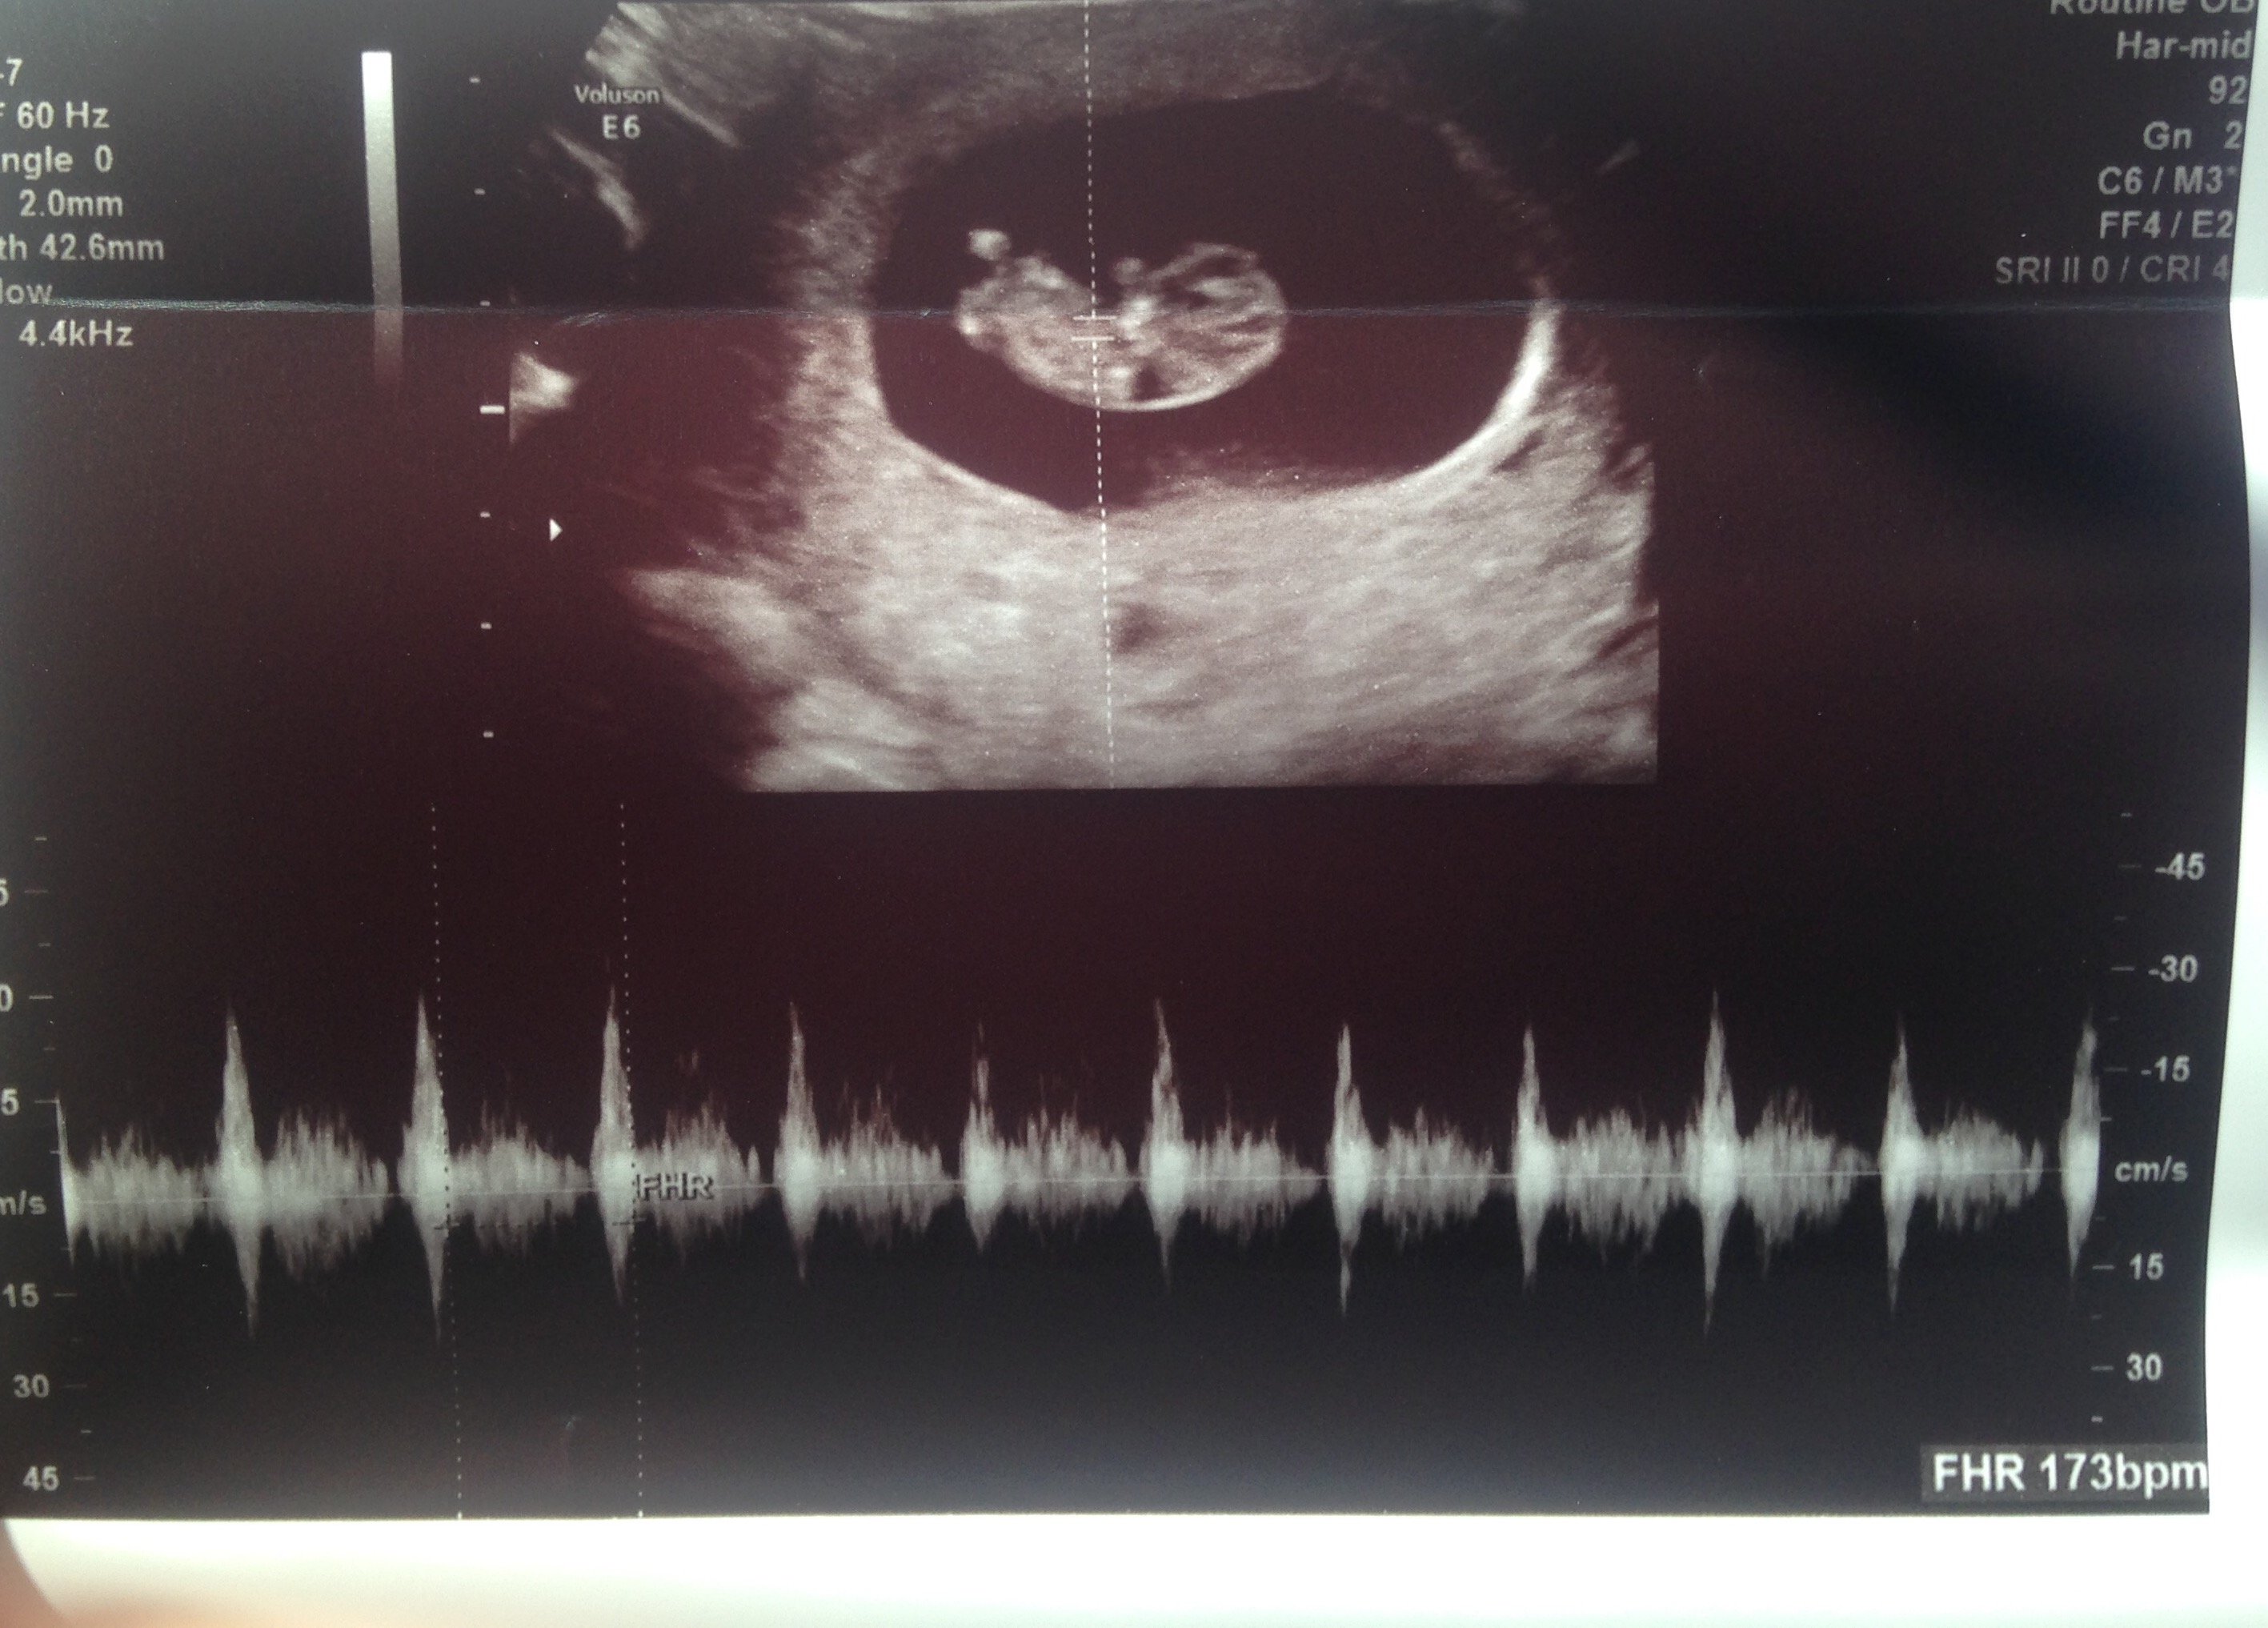

This ultrasound was done at 9w 3d. 12w 1d today . Wish I would have had one done a little further along to see something more . Fhr at 173 bpm. This is baby #2 we're really stoked

10 weeks and 2 days:) BMP was 175 it was AMAZING to see our little peanut dancing around. Very active!! This was our first ultra sound and it was spectacular:)

12w 1d today . Wish I would have had one done a little further along to see something more . Fhr at 173 bpm. This is baby #2 we're really stoked